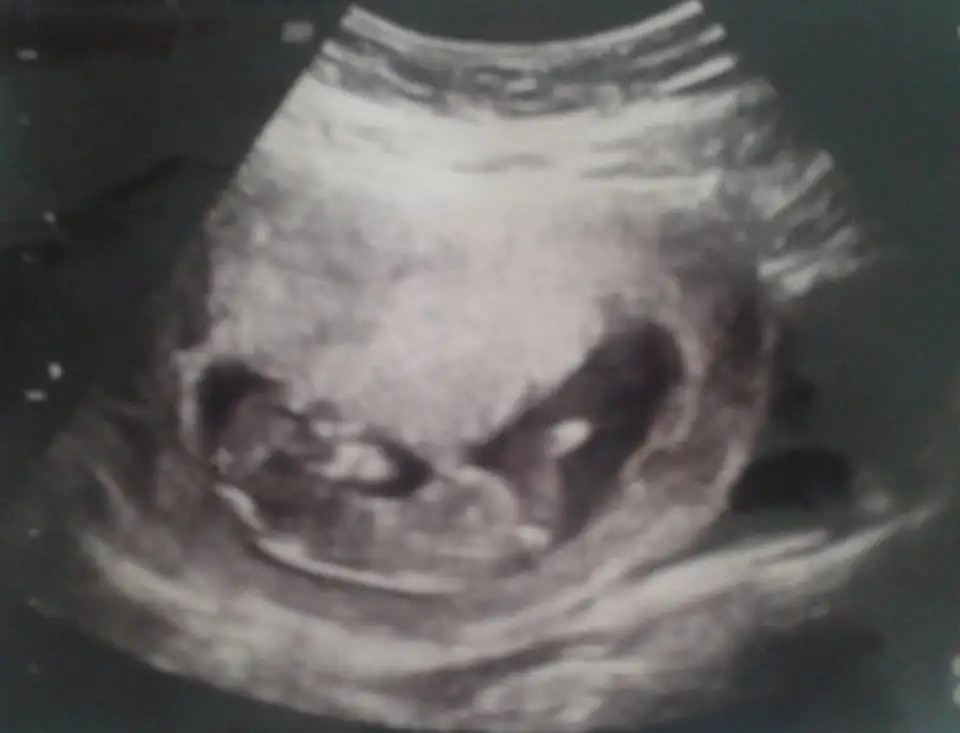

Merhaba biz bugün cinsiyetimizi öğrendik erkek dedi doktor Allah’ımın izniyleNubu kız görünüyor kafa şekli erkek görünüyorpozisyon değiştirmiyorsa nubu kız gibi

Selam doğru tahmin erkek dedi doktor bugünErkek gibi

Evet net değildi kafa şekli erkek dedim ikisinin arasında kaldımMerhaba biz bugün cinsiyetimizi öğrendik erkek dedi doktor Allah’ımın izniyle